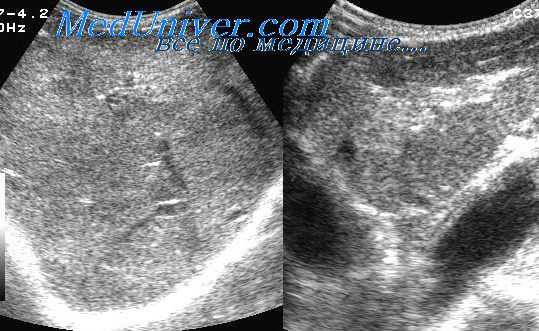

(Левый) У пациента с поликистозной болезнью печени на поперечном УЗ срезе во всех сегментах печени определяются многочисленные кисты. Видно, что каждая киста создает заднее акустическое усиление.

(Правый) У пациента с метастазирующей карциноидной опухолью а поперечном УЗ срезе живота в печени определяются множественные округлые гомогенные гиперэхогенные метастатические узелки. Вокруг печени видно большое количество асцитической жидкости. (Левый) У пациента с муцинозным раком ободочной кишки на поперечном УЗ срезе определяются множественные крупные гиперэхогенные метастазы, содержащие диффузно эхогенные очаги кальциноза. Обратите внимание на отбрасываемые кальцинатами акустические тени.